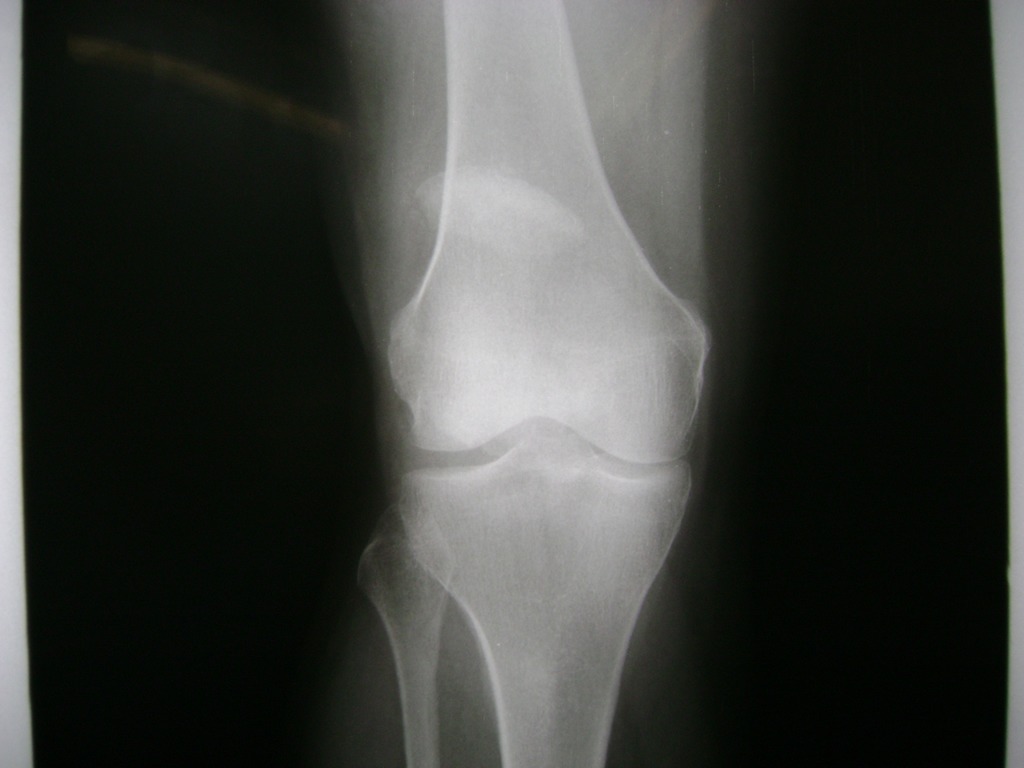

La artroscopia de rodilla es un cirugía en el cual la estructura interna de la articulación es examinada ya sea para realizar un diagnostico o para realizar un tratamiento, este procedimiento se realiza utilizando un instrumento parecido a un pequeño tubo llamado artroscopio.